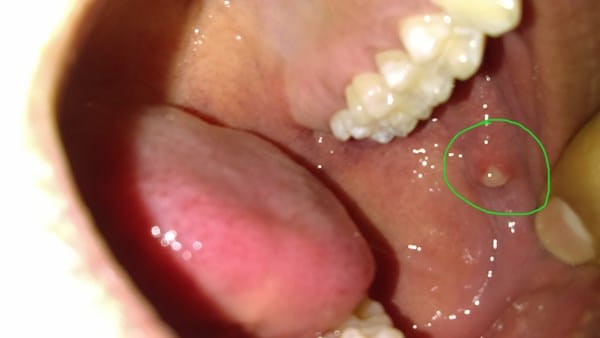

¿Absceso? Por dentro de mi mejilla

Desde el día de ayer tengo como un absceso, no se como más llamarlo, que me molesta bastante, es por la parte interna de la mejilla (dentro de mi boca)

Hola Mirna, yo creo que es litiasis salival lo que tiene el chico de la foto. A mi me salió algo parecido y buscando en internet, me di cuenta que eso era lo que yo tenía. la litiasis salival es cuando ocurre una obstrucción en una glándula salival o de su conducto excretor. A consecuencia se inflama esta glándula causa dolor puede salir pus. Aquí puedes leer mas sobre la litiasis salivalhttp://www.bachur.com.ar/litiasis-de-glandulas-salivales-menores/ - Yeye Pop

En este link se puede ver la glándula parótida inflamada.https://gacetadental.com/2009/02/cura-no-quirrgica-de-una-litiasis-parotdea-mediante-succin-en-stenon-solucin-ideada-a-propsito-de-un-caso-31698/ - Yeye Pop